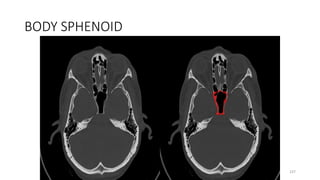

BODY SPHENOID